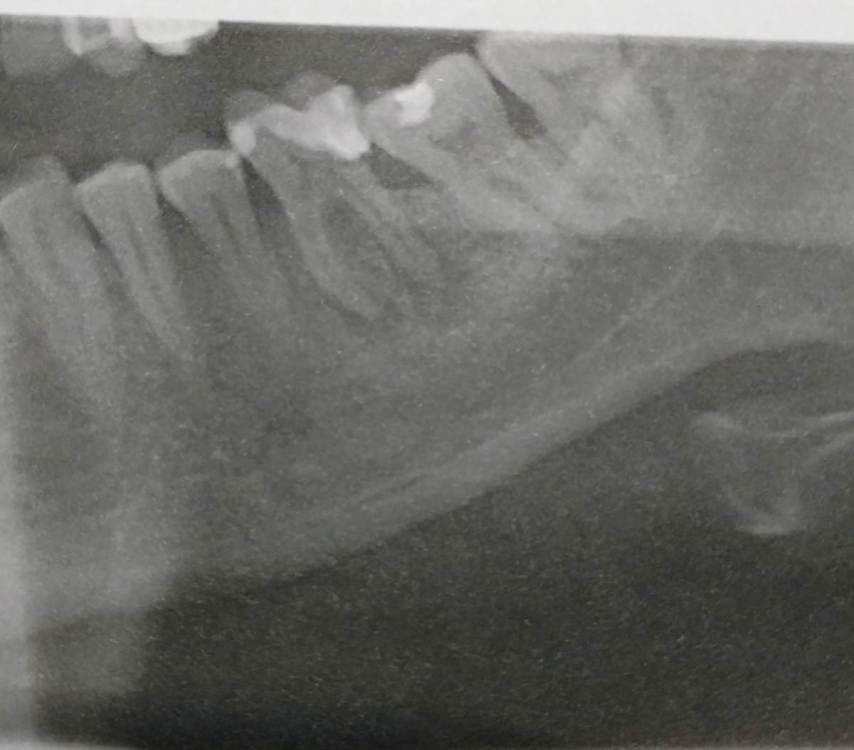

serov Опубликовано 17 декабря, 2023 Поделиться Опубликовано 17 декабря, 2023 Добрый вечер. В пятницу заболел зуб, вечером сделал снимок . На прием только на вторник записали , зуб болит и припухла щека, боль ноющая, постоянная , Год назад лечили глубокий кариес. Спасибо заранее Ссылка на комментарий

Doc Опубликовано 17 декабря, 2023 Поделиться Опубликовано 17 декабря, 2023 Мне кажется, что полечить можно попробовать, но без гарантий. Помимо проблем с каналами есть уходящий глубоко кариозный процесс в дистальной части зуба, который может потом вызвать затруднения в установке коронки. А на мертвый зуб она, скорее всего, понадобится. Так что либо лечить, но без гарантий, либо менять на имплантат с гарантией. Опять же, по одному снимку поставить диагноз и назначить лечение нельзя. Врач должен лично все осмотреть и только потом сделать какие-то выводы. Еще вопрос, наверху над этим зубом зуба давно нет? Ссылка на комментарий

Doc Опубликовано 17 декабря, 2023 Поделиться Опубликовано 17 декабря, 2023 1 час назад, serov сказал: Doc спасибо за ответ. Зуба сверху нет года 3-4 уже наверно Я думал, что дольше. Видимо, еще несколько лет он был в таком разрушенном состоянии, что нижний все это время выдвигался. В общем, эту проблему тоже решать нужно. Ссылка на комментарий